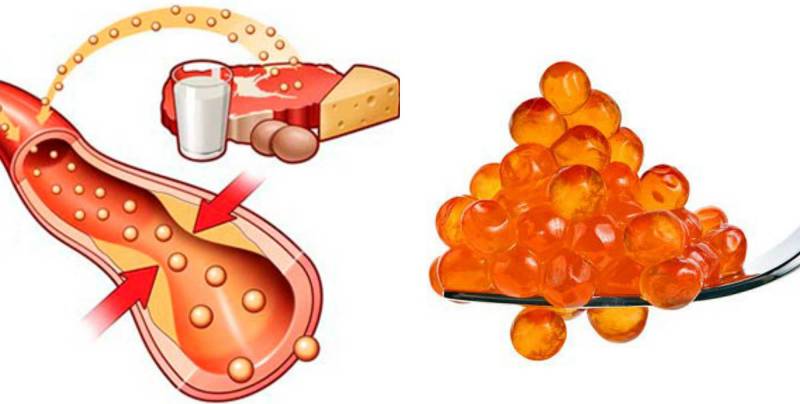

Холестерин в организме: влияние и функции (схемы и диаграммы)